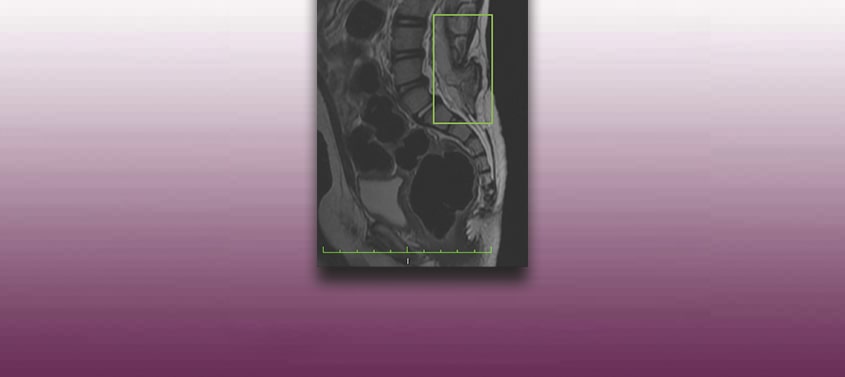

Moelle attachée avec spina bifida occulte ou Occult tethered cord syndrome

Dernière actualisation: 20/03/2026, Dr. Miguel B. Royo Salvador, Membre du Conseil de l’Ordre des médecins 10389. Neurochirurgien et Neurologue. Définition Dans des conditions normales, la moelle épinière est soutenue dans le canal vertébral uniquement par les ligaments dentés et le filum terminale, un ligament qui uni le cône médullaire avec les premières vertèbres du coccyx. […]